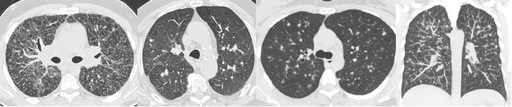

Verre dépoli

GHAYE B. - 2021 - UCL

Cardio-thoracique DES SPECIALITE